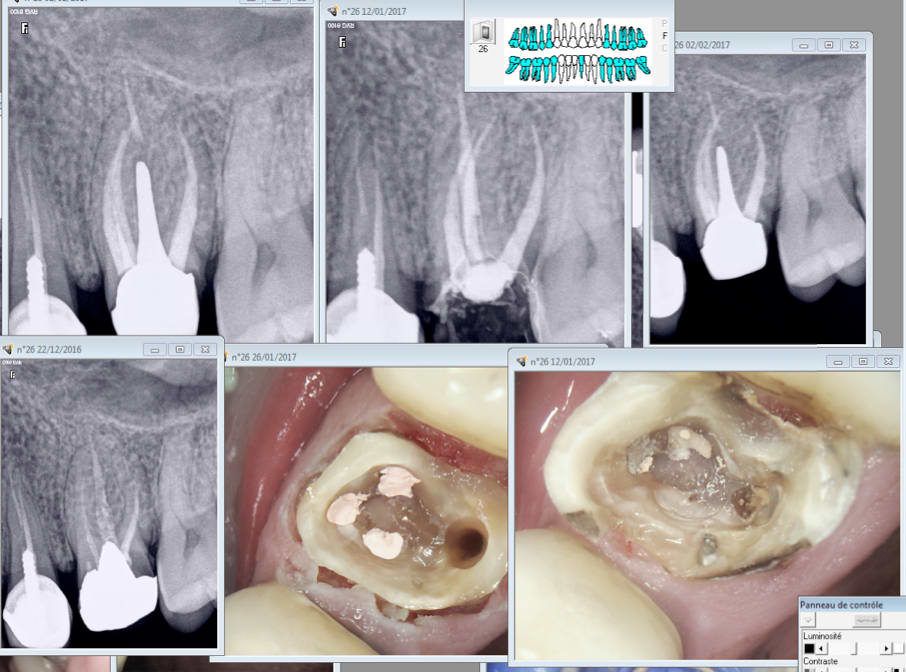

Capture d écran 2017 02 01 13.11 - Eugenol

Capture d écran 2017 02 01 15.45 - Eugenol

Capture d écran 2017 02 01 14.04 - Eugenol

Capture d écran 2017 02 01 15.37 - Eugenol